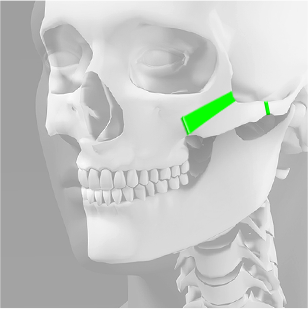

광대뼈는 사각턱뼈에 비해 작고 약하고 얇으며,

얼굴뼈 중에서 가장 강한 힘을 받기 때문에

광대뼈 축소수술은 안면윤곽 수술 중에서 가장 어려운 수술입니다.

김태규 대표원장이 직접 개발한 리프팅 3D 광대회전술은 브라운만의

우수한 기술력을 통해 안전하고 효과적인 광대 축소술이 가능합니다.

얼굴 전체의 조화로운 비율을 고려하는 것이 중요 Point

1. 귀 앞부분의 옆광대를 절골

2. 앞광대 안쪽 부분의 광대뼈를

사다리꼴로 모양으로 절골해서 제거

3. 남아 있는 광대뼈를 안쪽, 위쪽, 뒤쪽으로

이동시켜서 뼈의 절단면을 서로 밀착

4. 티타늄 플레이트와나사를 사용하여

앞쪽과 뒤쪽 모두 튼튼하게 고정